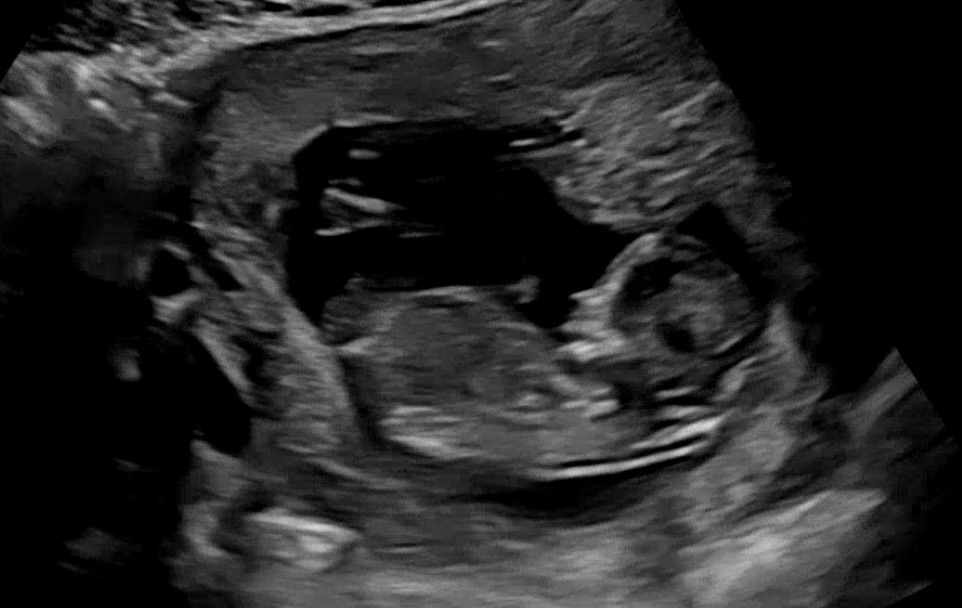

한달만에 본 아가는 어엿한 사람의 모습을 갖추었더라구요 😊😊 피검사 결과는 아직 안나왔는데 별일 없기를🙏🙏 12w3d 크기 5.8 심박수 165 투명대 1.24 좌우뇌ok 코뼈ok 아기가 머리가 좁은곳(?)에 끼어있어서 생각보다 각도법 자세가 잘 안나오더라구요 ㅠ 선생님께 계속 봐달라고 할수도 없는 노릇이고ㅠㅠ 겨우 옆모습 나온거 캡처해서 올려봅니다~ 혹시 각도법 보이신다면 댓글 부탁드립니다😁